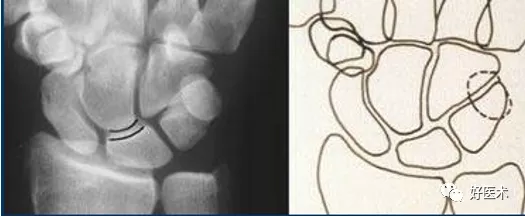

- 月骨-三角骨間隙平行關係缺失致掌骨弧線 I and II 中斷。

- 月骨和舟骨平行,而與其他腕骨不平行。

- 舟骨縮短提示向掌側傾斜。

- 月骨平行於舟骨,其三角形狀提示為掌側傾斜所致。

- 近排腕骨不是一個整體,因為弧線 I 中斷。

側位顯示月骨向掌側傾斜

最後診斷:掌屈不穩伴月骨-三角骨關節脫位。